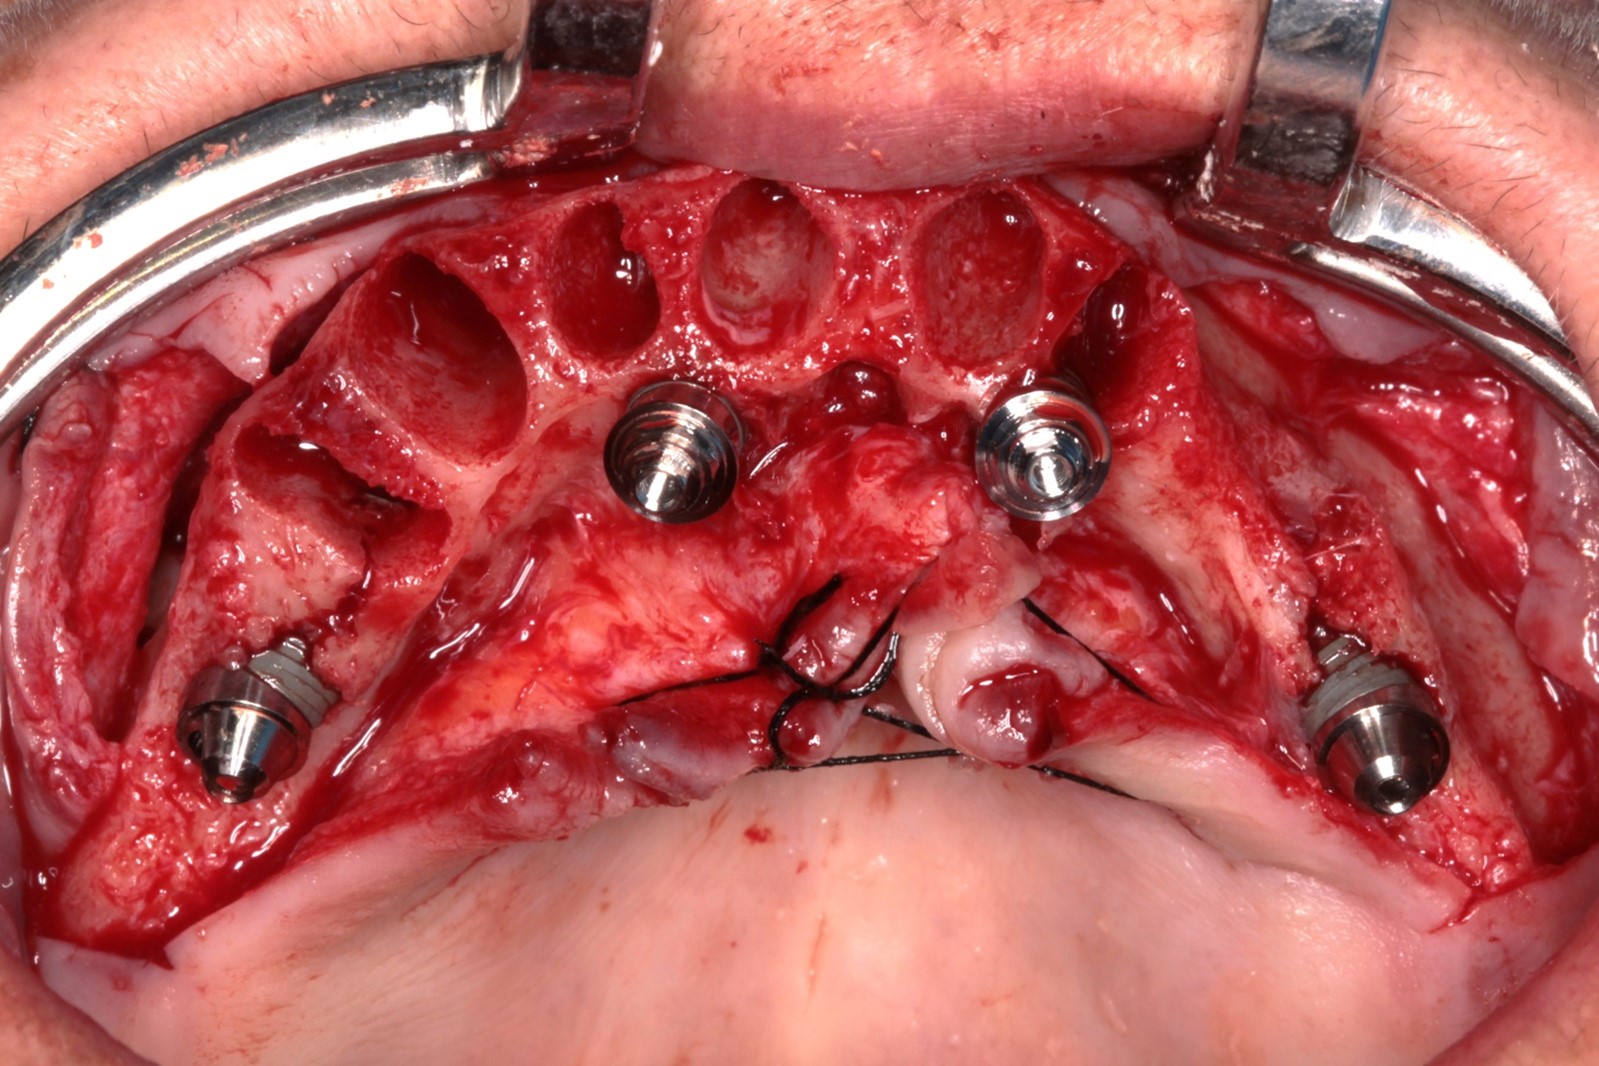

Todos os implantes atingiram um torque de 80 N, possibilitando a realização de carga imediata. Mini pilares retos com transmucoso de 2mm foram instalados nos implantes anteriores e mini pilares angulados de 30 graus com transmucoso de 3mm nos distais, corrigindo a ajuste dos implantes e sustentando o assentamento passivo da barra.

FIG. 08 – Instalação dos mini pilares angulados de 30 graus nos posteriores e retos nos anteriores.